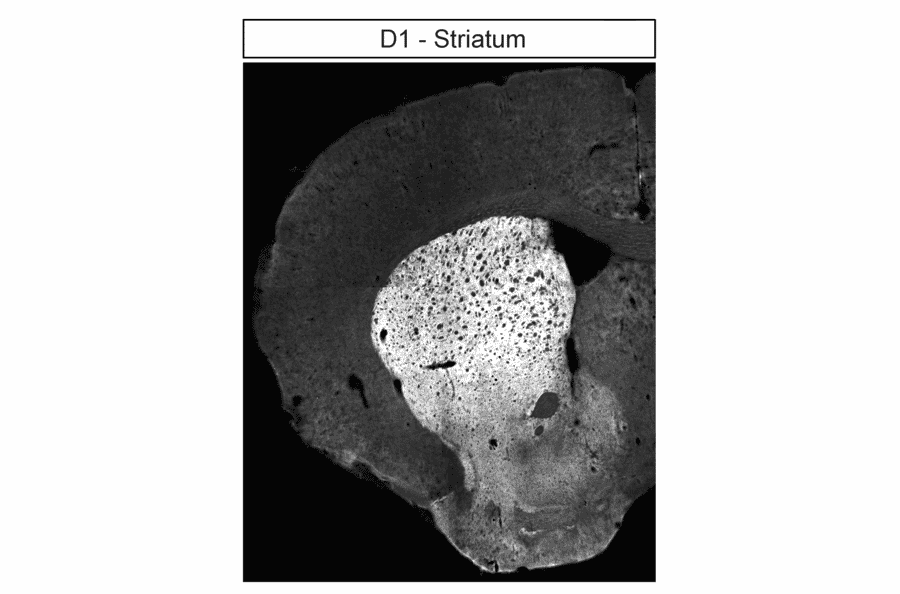

Localization of Dopamine Receptor 1 (DRD1) and Dopamine Receptor 2 (DRD2) in striatum by immunohistochemistry. Striatal sections were dewaxed, microwaved in citric acid, and incubated with either anti-DRD1 antibody (A334475) at 1:100 (left panel) or anti-DRD2 antibody (A334504) at 1:100 (right panel), followed by biotinylated anti-rabbit IgG and avidin-biotin solution. Color was developed with 3-amino-9-ethylcarbazole (AEC), and sections were counterstained with hematoxylin.